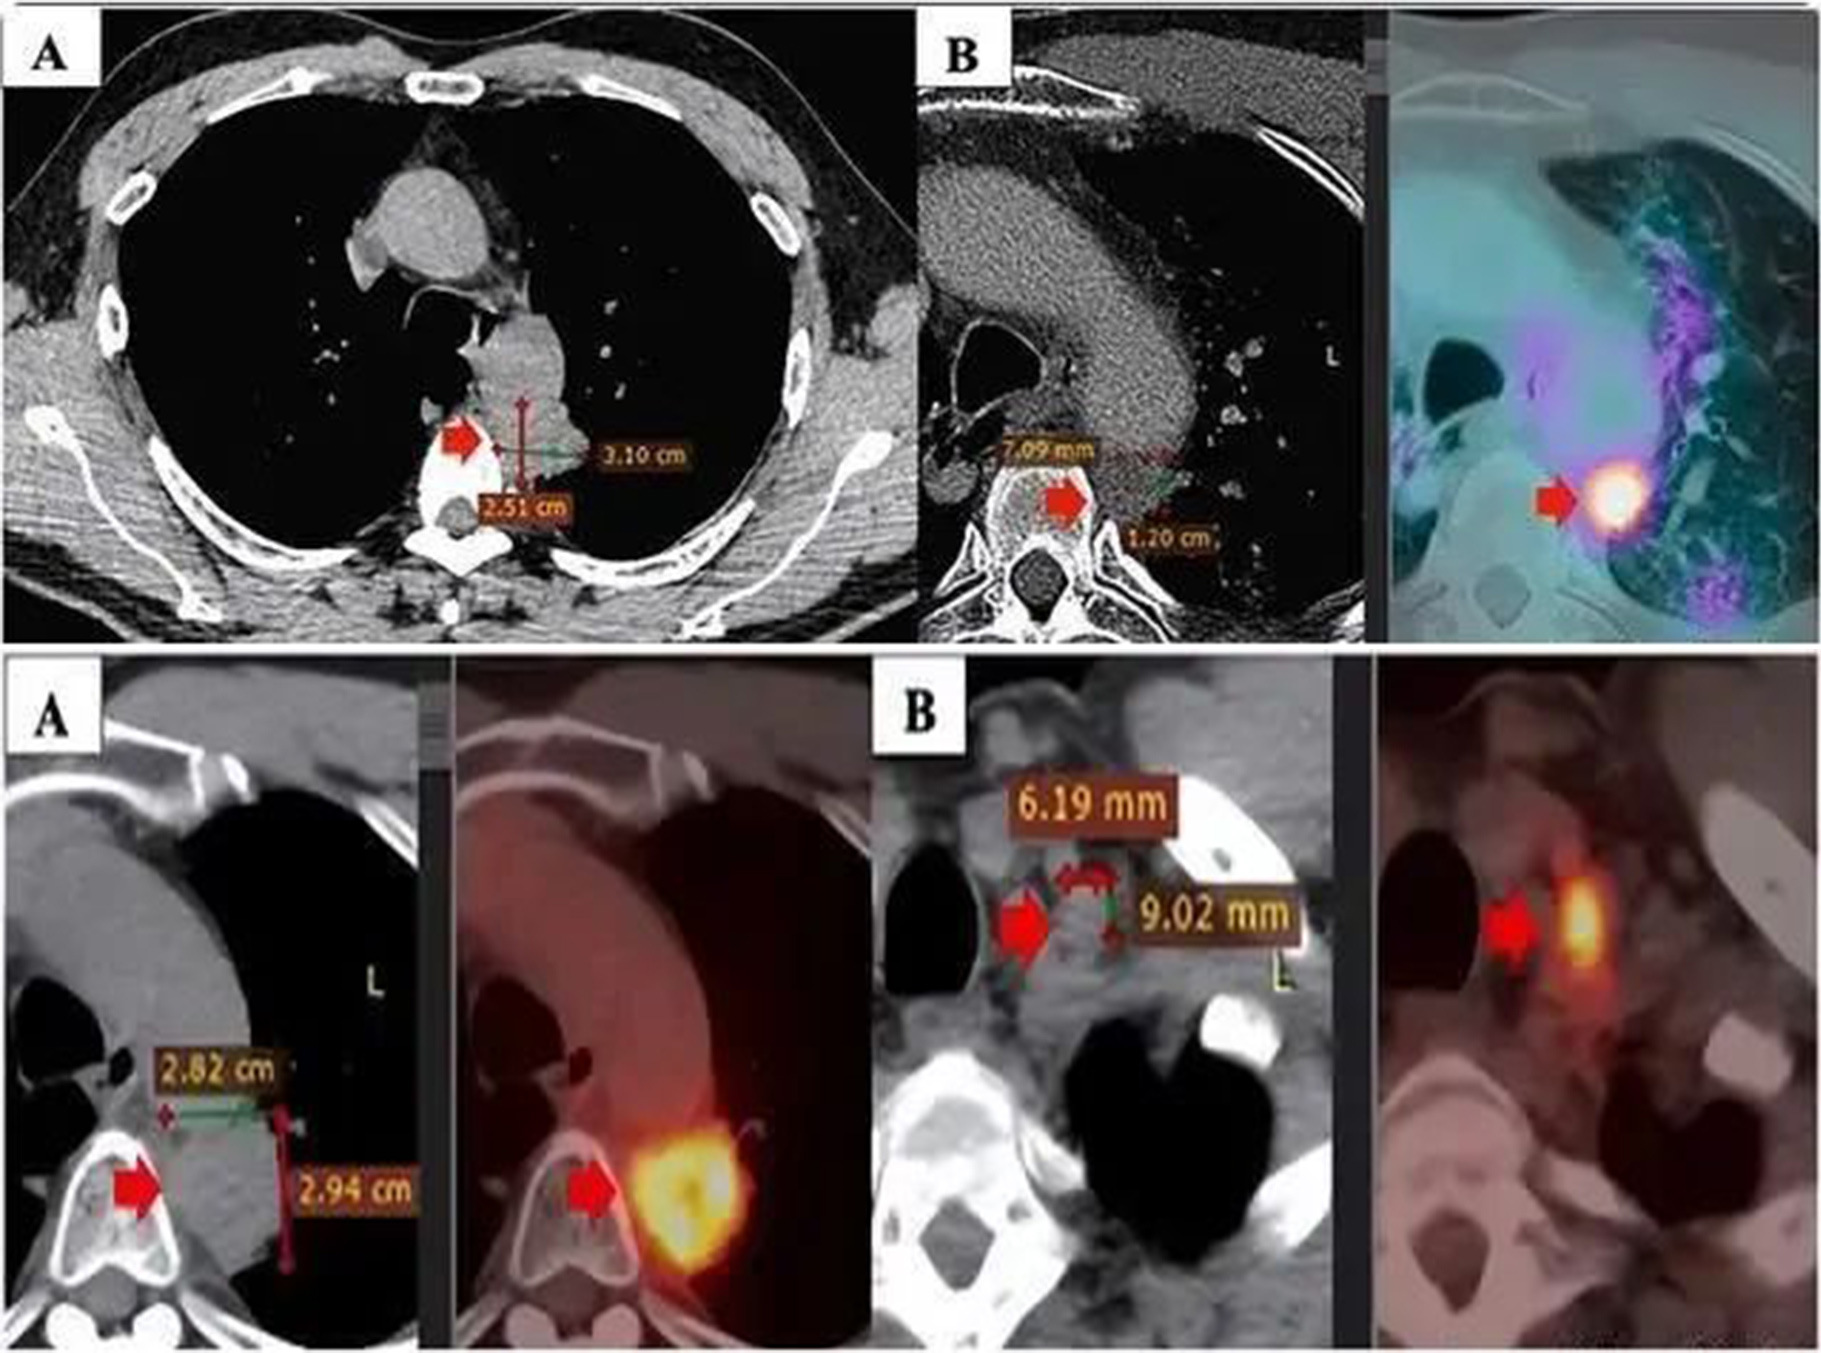

从2019年6月到2019年12月,患者接受了第三周期的3个周期的卡铂650mg(AUC5)加紫杉醇300mg(175mg/m2)联合放疗的一线治疗。症状获得了部分缓解,临床症状和副临床症状都有所改善。患者的正电子发射断层扫描(PET)/CT扫描显示原发肿瘤的大小减小(12×7mm),肿瘤标志物值于2019年12月恢复正常。

尽管如此,该疾病在2020年5月继续发展。PET/CT扫描显示原发性肿瘤大小为28×29mm,标准化摄取值(SUVmax)11.2,与纵隔胸膜和主动脉粘连。此外,左侧锁骨上淋巴结的大小为9×6mm,左侧门中的一些小淋巴结的尺寸小于10mm。PD-L1表达阳性(25%),接受4个周期的阿利姆塔(500mgx2)、卡铂(150mgx2,450 mgx1)、可瑞达(4mlx2)的二线治疗。然而,他的病情在2020年6月的 PET/CT 扫描中表现不稳定。由于疾病进展,患者的治疗方案发生了变化。

2021年3月和2021年9月进行的PET/CT扫描显示,与联合治疗前相比,原发肿瘤的大小显著减少。此外,没有发现两侧的纵隔淋巴结和锁骨上淋巴结。